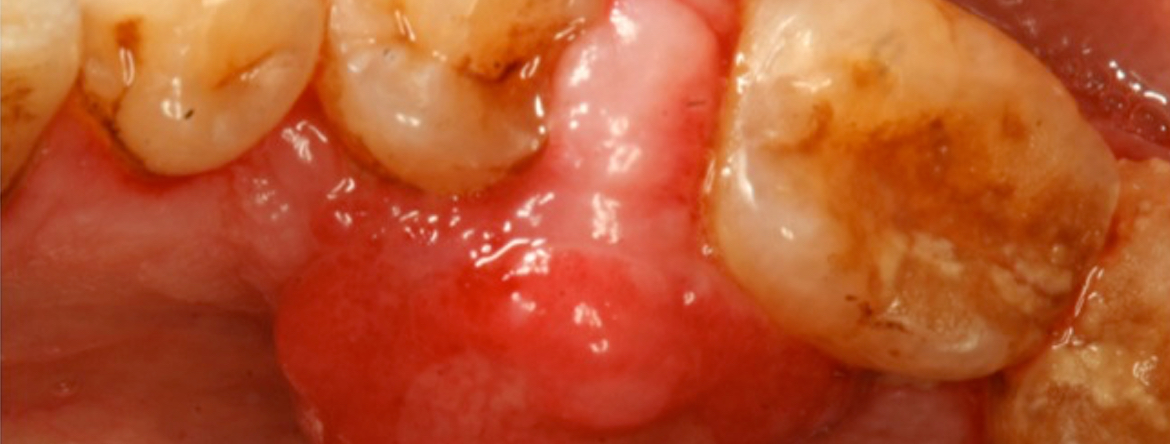

A biópsia é um procedimento cirúrgico que visa a obtenção de tecidos de um indivíduo vivo para análise histológica. O exame anatomopatológico auxilia na definição do diagnóstico, facilita a determinação do prognóstico de lesões malignas e potencialmente malignas, contribui para a instituição do tratamento ou avaliação da sua eficácia e constitui um documento com valor médico-legal.

Durante esta conferência será realizada uma descrição dos procedimentos associados às diversas técnicas de biopsia (excisional, incisional, aspirativa e exfoliativa), bem como uma revisão das principais lesões e patologias da cavidade oral com indicação para biopsia, devidamente ilustrada com casos clínicos.